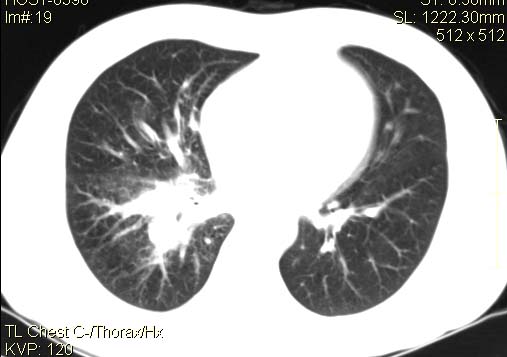

以下是引用qingyuan在2007-4-17 14:19:00的发言:[br]右肺下叶外侧后段胸膜下区节结样病变、分叶、内可见空洞,壁厚薄不均,胸膜凹陷、肺门周围区纹理增粗、僵硬、并近似小结节样改变,肺门区软组织节结、纵膈淋巴结肿大,患者病史长、抗炎治疗无好转炎性改变基本排除,考虑:右肺下叶周围型肺癌伴纵膈及右肺门区淋巴结转移、肺内淋巴管受侵。